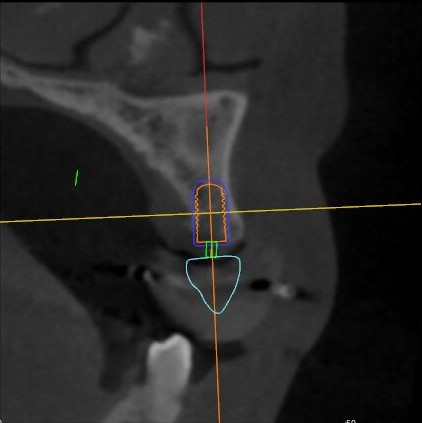

冠狀面視圖

矢狀面視圖

軸狀面視圖

三維視圖

根據(jù)患者CT顯示,使用種植導(dǎo)航軟件設(shè)術(shù)前手術(shù)方案??紤]到患者拒絕手術(shù)摘除上頜竇囊腫等因素,此次手術(shù)選用了Straumann骨水平4.10*8.0mm的植體,植體末端位點(diǎn)設(shè)計(jì)距上頜竇底壁2mm處的同時(shí)兼顧種植方向和修復(fù)間隙,來(lái)達(dá)到理想的效果。